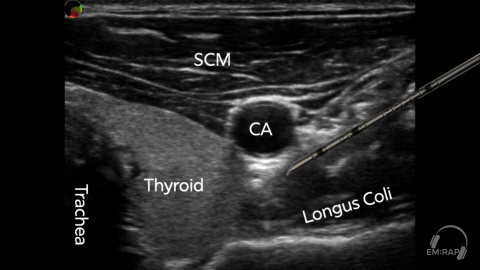

Stellate Ganglion Block